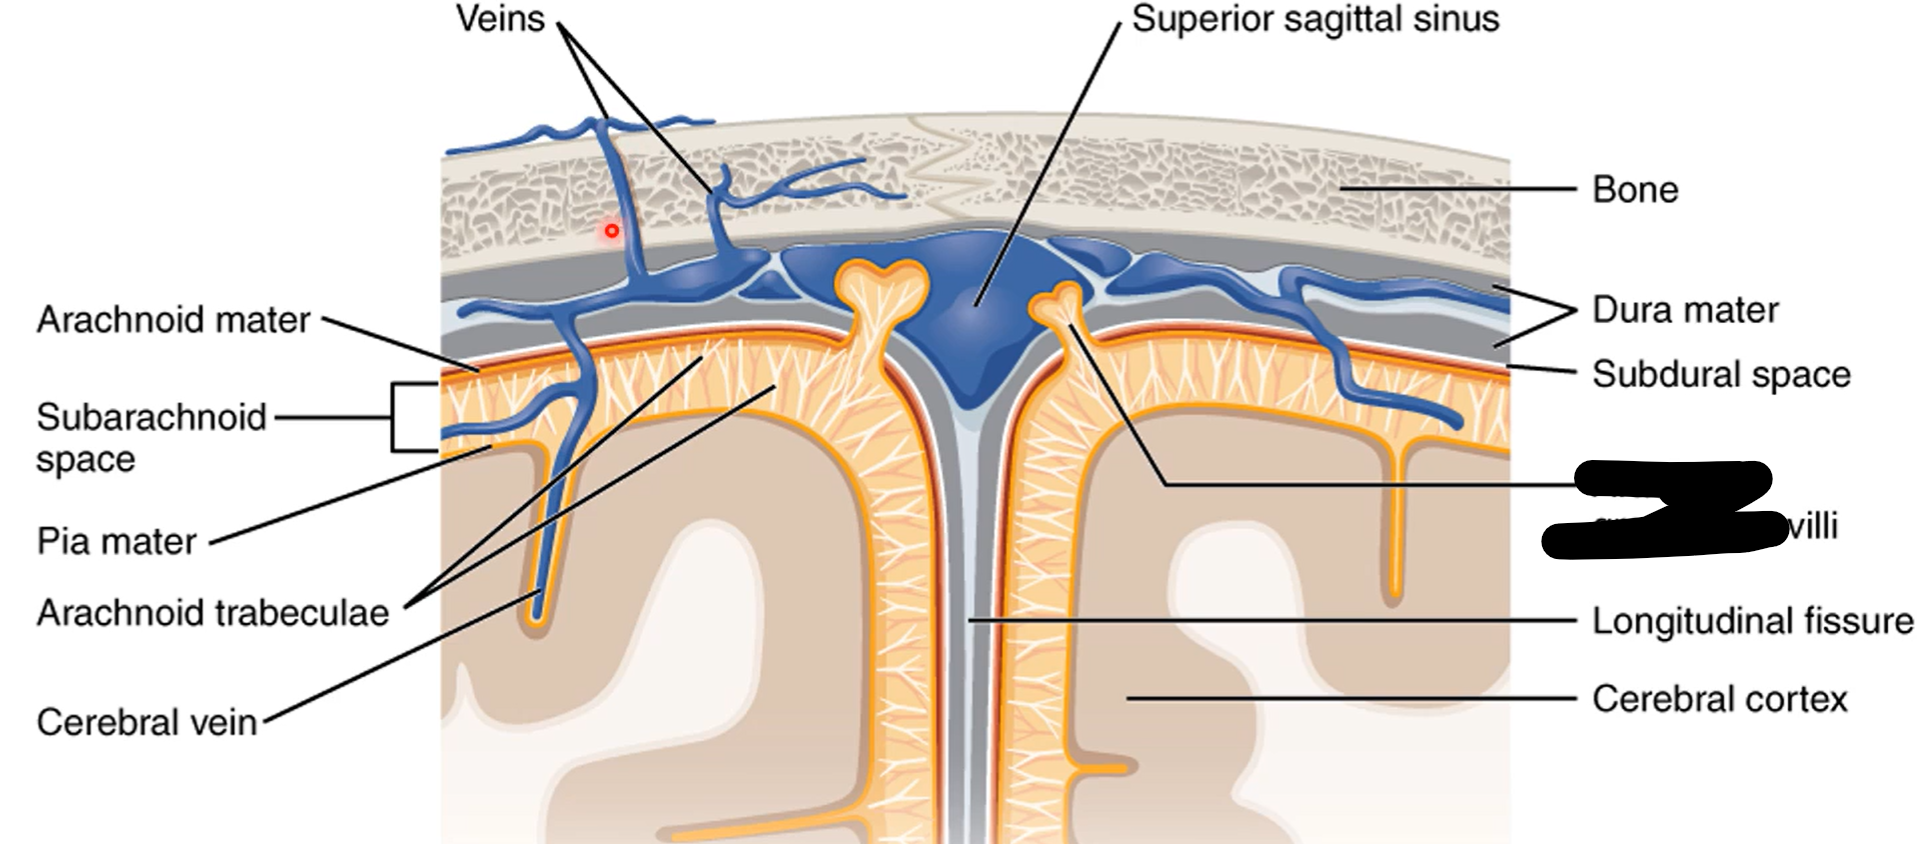

How many layers of meninges

3

Layer of meninges from superficial to deep

Dura mater

Arachnoid mater

Pia mater

What are the two layers of dura mater?

Periosteal dura mater

Meningeal dura mater

What does the pia mater follow?

Sulci and gyri

Where is epidural and subdural space?

In spinal cord (contains fat) or brain (potential space)

What does epidural space separate in spinal cord?

Between vertebrae and dura mater

Epidural space (contains fat)

Subdural space (contains CSF)

What does subdural space separate?

Dura mater and arachnoid mater

What does subarachnoid space separate?

Arachnoid mater and pia mater

What lies between meningeal dura mater and periosteal dura mater?

Dural venous sinuses

What does CSF flow back into dural venous sinuses by?

Arachnoid granulations

What are those grey projections called?

Arachnoid trabeculae